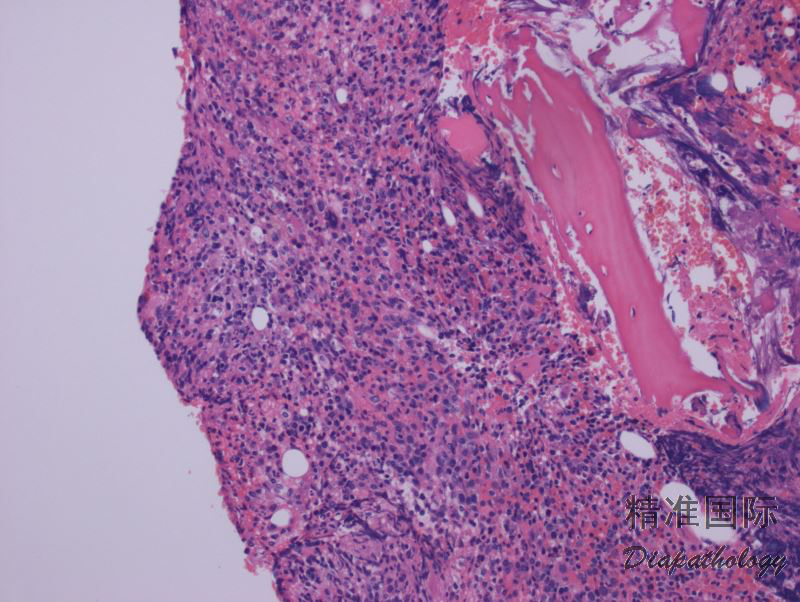

外周血肿瘤细胞多少不等,从少量(焖燃型)到显著升高(急性型)。淋巴结类似白血病样侵润,窦内侵犯也常见。皮肤呈血管周围侵润,常累及表皮,有时真皮广泛侵润形成肿瘤结节并延至皮下。

肿瘤细胞形态大小多样,但急性型具有典型的细胞形态(多数患者在病程某阶段表现为急性型),其特点是多叶状细胞核如花瓣样,称为花样细胞;染色质致密、深染,但花样细胞通常无明显核仁;胞质嗜碱性,可见胞质空泡。有的病例(主要是慢性和闷燃型)淋巴细胞大小形态可类似正常淋巴细胞。